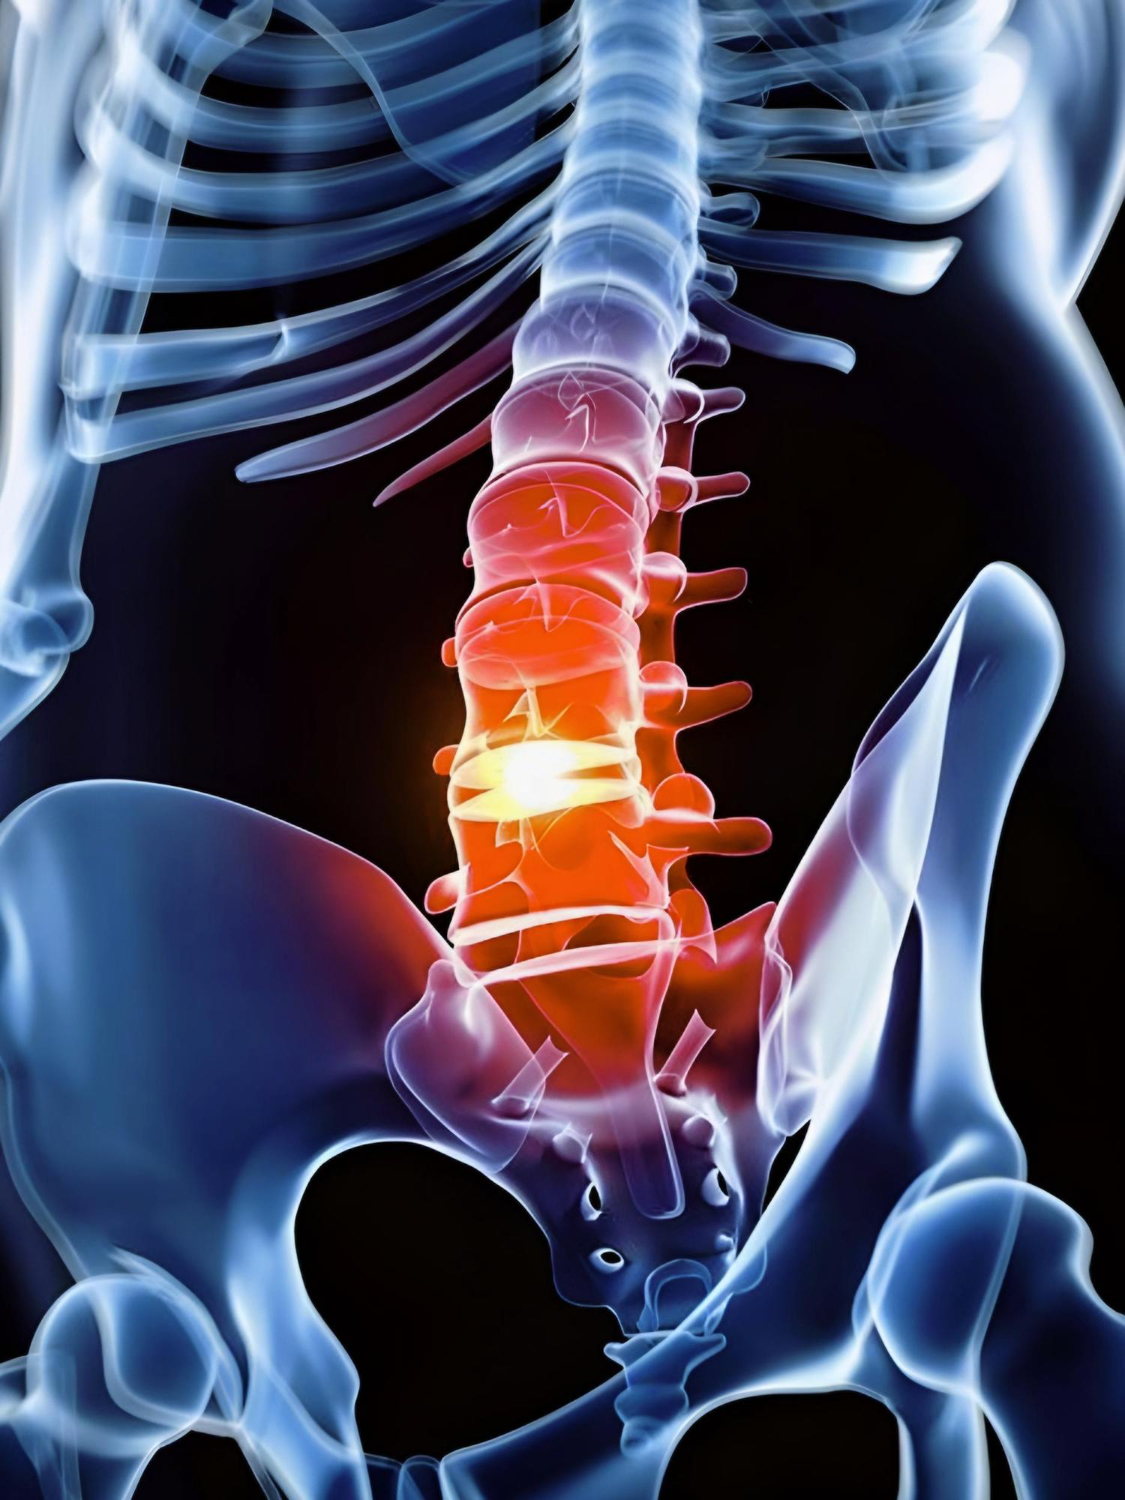

Tumores da medula espinhal

Os tumores da medula espinhal podem causar dor, fraqueza, alterações de sensibilidade e dificuldades motoras, já que afetam diretamente a condução dos impulsos nervosos. O diagnóstico precoce é essencial para evitar complicações e definir a melhor forma de tratamento. Na Clínica N3, contamos com especialistas em neurologia e neurocirurgia preparados para identificar e tratar esses casos de forma personalizada, sempre com foco na segurança, na recuperação funcional e na qualidade de vida do paciente.

A espondilolistese é uma condição em que uma vértebra da coluna desliza sobre a outra, podendo causar dor lombar, fraqueza, formigamento e limitação de movimentos. O diagnóstico precoce é essencial para evitar a progressão do quadro e definir o tratamento mais adequado. Na Clínica N3, oferecemos avaliação especializada e acompanhamento personalizado, com opções de tratamento clínico e cirúrgico, sempre com foco em aliviar os sintomas, restaurar a função e garantir qualidade de vida ao paciente.